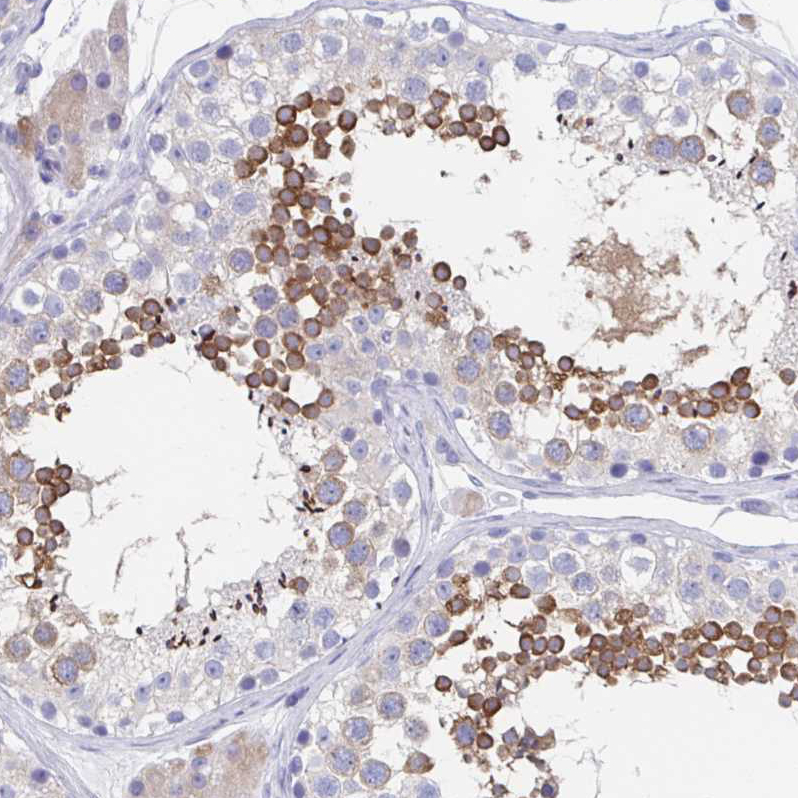

Immunohistochemistry analysis in human testis and liver tissues using HPA036125 antibody. Corresponding SHCBP1L RNA-seq data are presented for the same tissues.